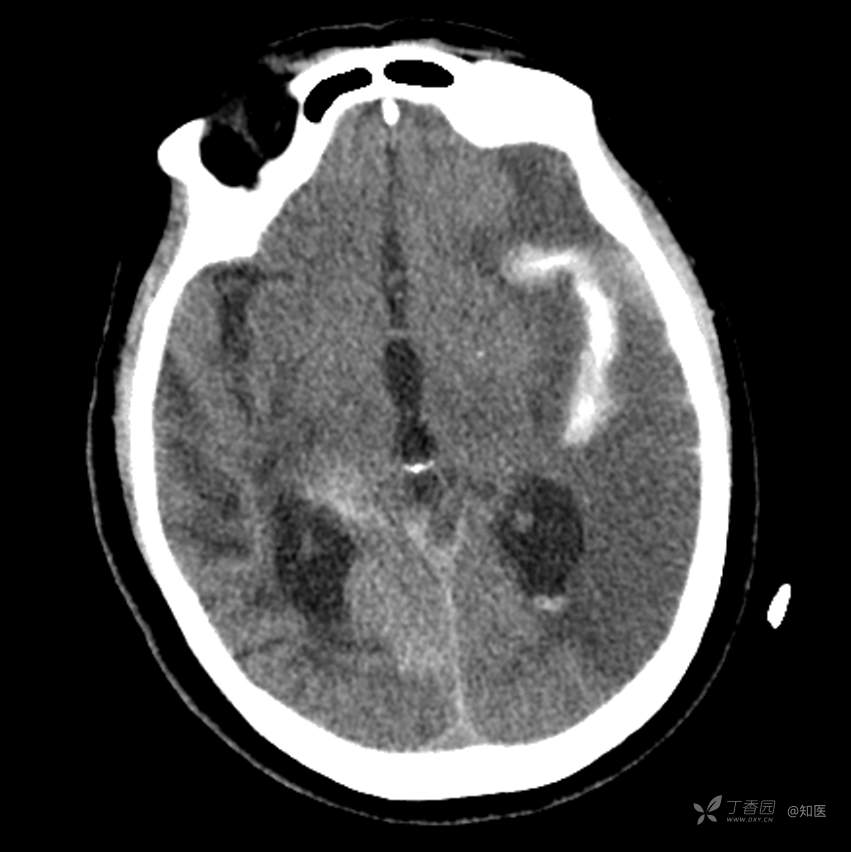

4-22日查房患者呈昏睡状,混合性失语,右侧肢体肌力障碍较入院时加重,胃肠减压引流物为深黄绿色液体,量约150ml。查体:GCS 9分(睁眼反应 3分+语言 1分+运动 5分),NHISS评分23分(意识水平 2分+提问 2分+指令 1分+凝视 2分+面瘫2+左上肢 1分+右上肢4分+左下肢 2分+右下肢4分+语言 3分),昏睡状,查体欠合作,混合性失语,粗测智能查体不配合。双眼闭目紧,双侧球结膜水肿,双侧瞳孔等大等圆,直径约4.0mm,对光反射灵敏,眼球无自主运动,无眼震,右侧鼻唇沟浅,口角向左歪斜。咽部查体不配合。转颈、耸肩查体不配合。伸舌不配合。右上肢肌力1级,右下肢肌力2级,左上肢肌力3级,左下肢肌力4级,四肢肌张力减低。四肢深浅感觉及共济运动查体不配合。右侧巴氏征阳性,左侧巴氏征阴性。颈抵抗。双侧布氏征及克氏征均阴性。辅助检查:头颅+胸部CT:与前片(2021-4-21 13:57)对比,现片示:1、环池、桥前池及大脑镰后部及小脑幕高密度影,考虑出血,较前新发。2、额颞顶叶高低混杂密度影,考虑梗塞伴造影剂残留;左侧大脑中动脉走行区致密影,系术后改变;请结合临床。3、多发腔梗,脑白质脱髓鞘,脑萎缩。4、双肺间质性改变,双肺下叶纤维索条,双侧胸腔微少量积液征象,双侧胸膜增厚。5、主动脉及冠状动脉管壁多发钙化斑块。三线主任医师、二线主治医师查房后示:根据患者病史、体征及辅助检查,目前诊断:1.脑梗死出血转化;2.左侧大脑中动脉次全闭塞;3.左侧大脑中动脉支架植入术后;4.高血压2级(很高危);5.2型糖尿病;6.应激性溃疡伴出血。目前病情及治疗上需注意以下问题:1.患者出血转化,增加脱水剂剂量,调整为20%甘露醇 125ml 每8小时一次、甘油果糖 250ml 每12小时一次,同时结合患者球结膜水肿,白蛋白正常低值,今日给予补充人血白蛋白10g,注意监测电解质等变化。2.患者为蛛网膜下腔出血,给予泵入尼莫地平预防脑血管痉挛。3.患者左侧大脑半球见大片脑白质脱髓鞘,考虑脑白质营养不良,给予维生素B1、维生素B12、维生素C、维生素B6及依达拉奉改善微血管通透性;4.患者出现应激性溃疡伴出血,今日暂禁食,给予泮托拉唑抑酸及肠外营养补充,密切观察消化道出血情况,根据病情变化调整抑酸药物剂量及频次;5.患者卧床,今晨见明显痰多,给予化痰等对症处理,监测血常规及脓毒症2项指标。6.向家属再次告知病情,因患者高龄、既往高血压及糖尿病病史,此次治疗出现出血转化,存在意识障碍加深、病情加重可能。7.密切观察神经系统体征变化。遵嘱执行。